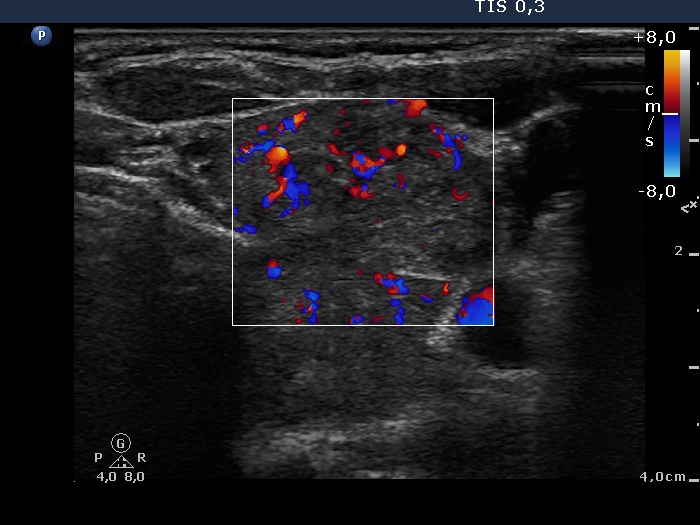

Ultrasonography. The thyroid was echonormal and contained multiple nodules. The right lobe was composed of an echonormal and a cystic nodule. A large moderately hypoechogenic nodule occupied almost the entire left lobe. It had irregular borders, was lobulated and displayed microcalcifications and intranodular vascularization. There were multiple enlarged lymph nodes in the left side of the neck.